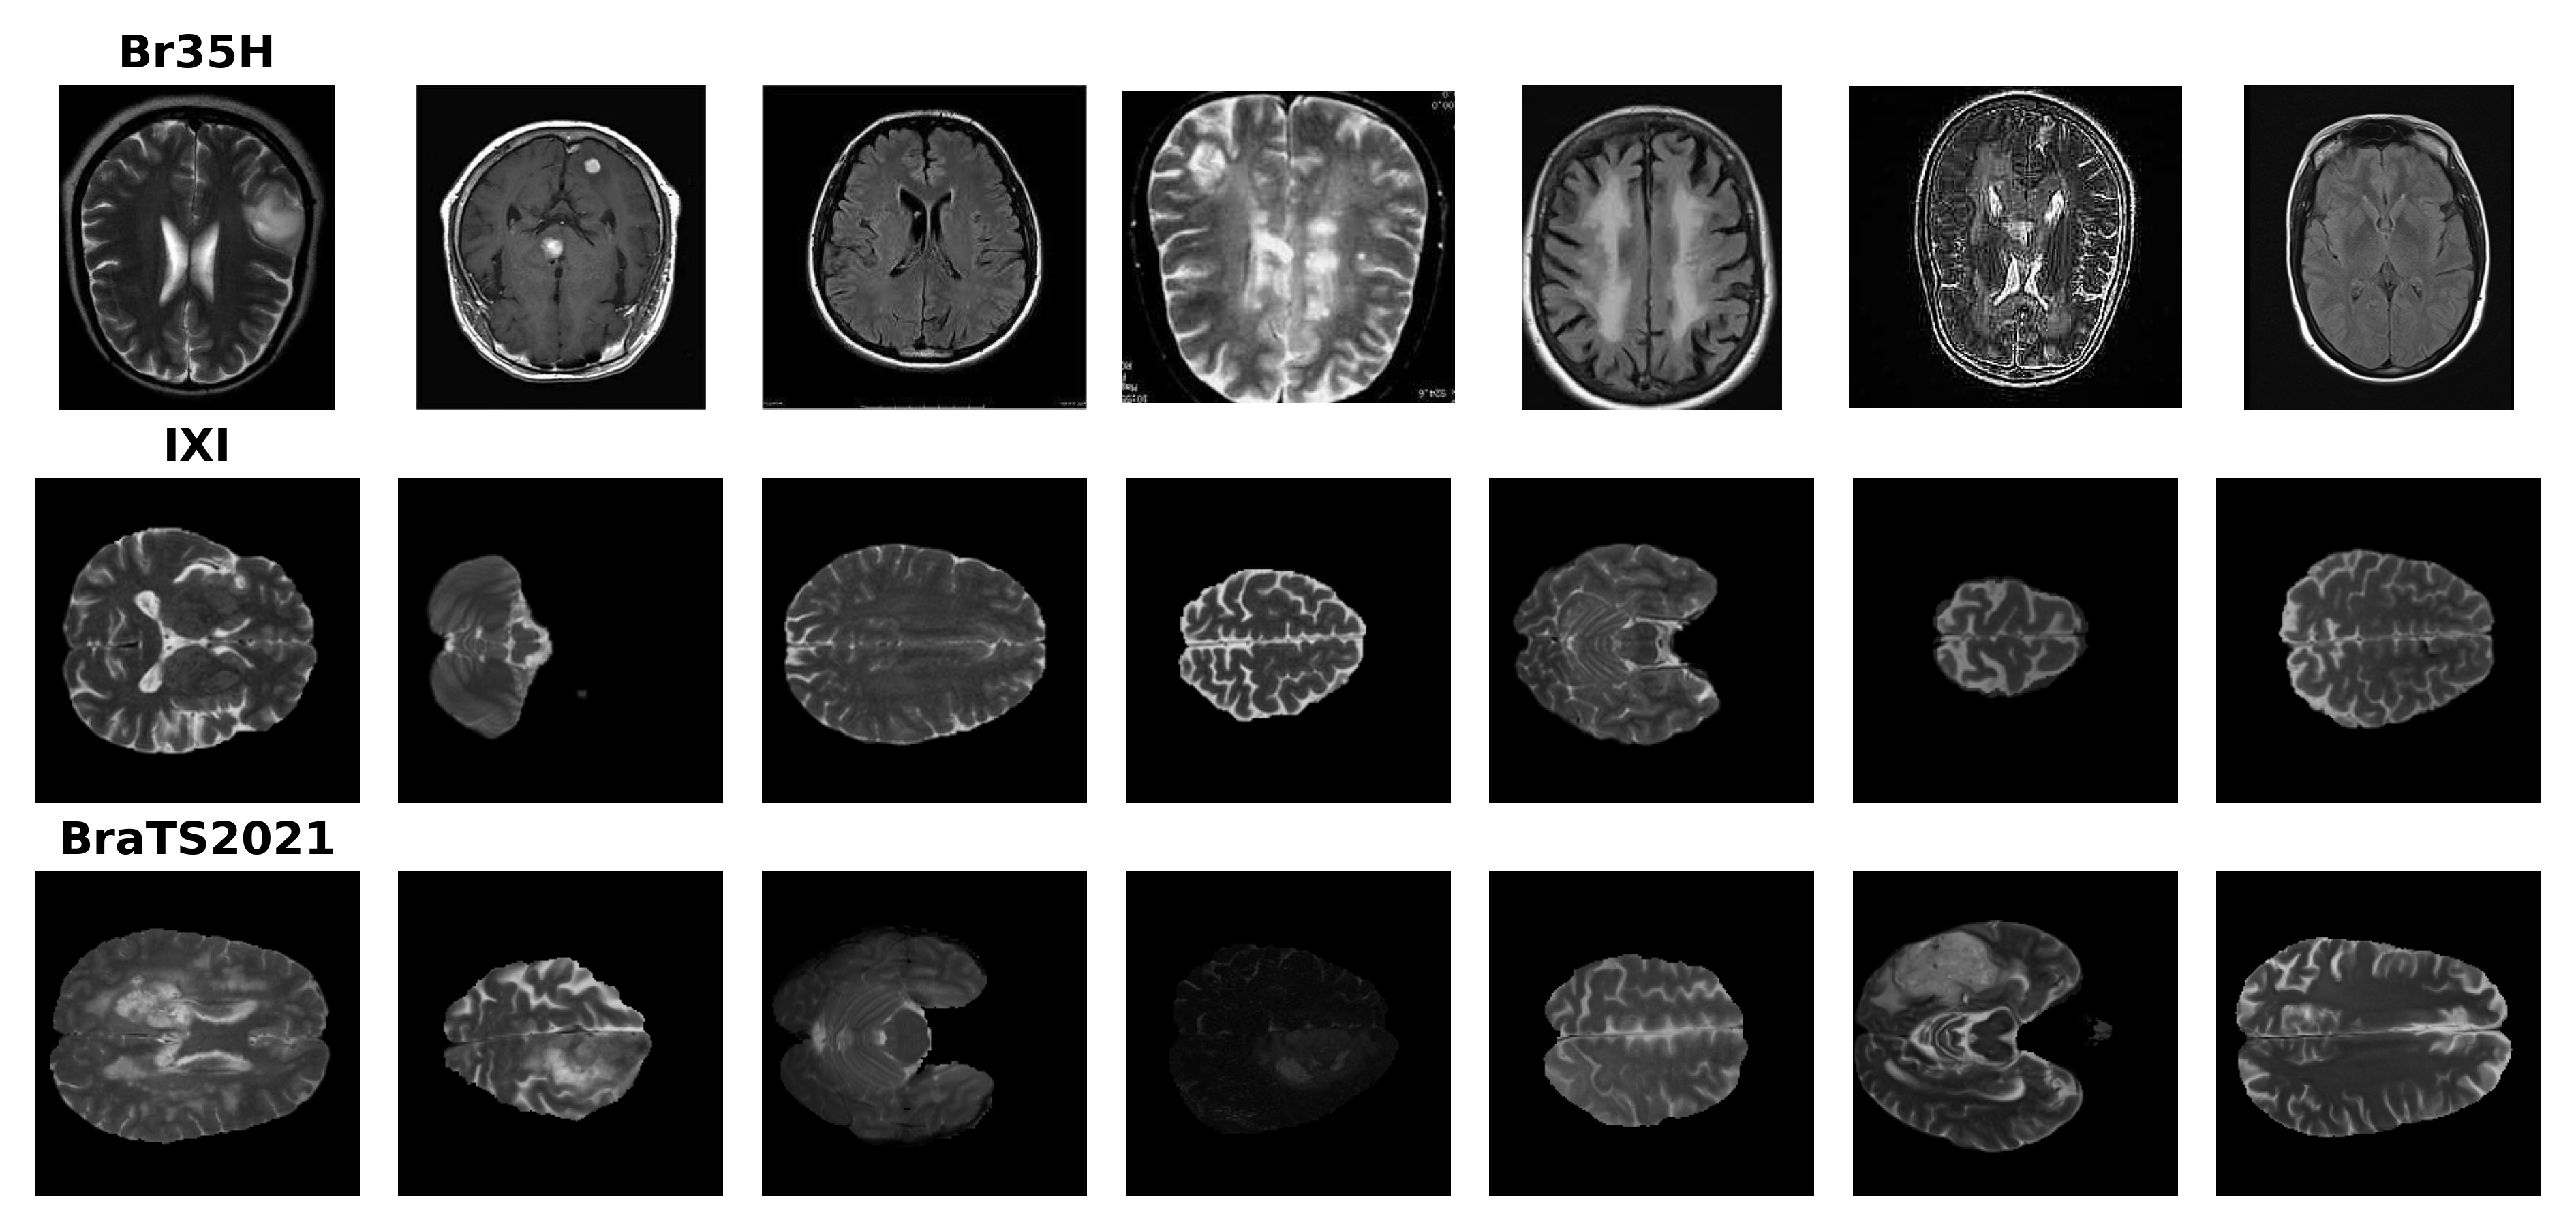

Br35H is a 2D brain MRI dataset on Kaggle [19]. It contains 1,500 2-D image slices that are tumorous and 1,500 images that are non-tumorous. We resized the non-tumorous images to 256x256 and used them to fine tune the pre-trained model. From Fig 1, we observe that images from Br35H are inconsistent, not skull-stripped, and represent only the central area. The IXI dataset [20] contains 576 healthy subjects from multiple institutions. The spatial resolution of all slices is 0.94×0.94×1.250.940.941.250.94\times 0.94\times 1.25 mm3𝑚superscript𝑚3mm^{3}, with an in-plane matrix size fixed at 256×256256256256\times 256, and the number of slice ranged from 28 to 136. We use the T2-weighted volumes for training. The BraTS2021 dataset [21, 22, 23] comprises a total of 1,251 subjects with Glioblastoma. These images are interpolated to 1×1×11111\times 1\times 1 mm3𝑚superscript𝑚3mm^{3} resolution, skull-stripped, and finally cropped to a fixed size of 240×240×155240240155240\times 240\times 155. We use the T2-weighted volumes for testing. Within this dataset, 251 volumes are designated for validation and 1,000 are used for testing. Samples from these three datasets are shown in Fig 1

Figure 1: Samples from datasets This figure displays samples from each dataset used in this study. Each row represents samples from a different dataset, providing a visual comparison of their characteristics and preprocessing differences. Samples from the IXI and BraTS2021 shown in this figure have undergone preprocessing.